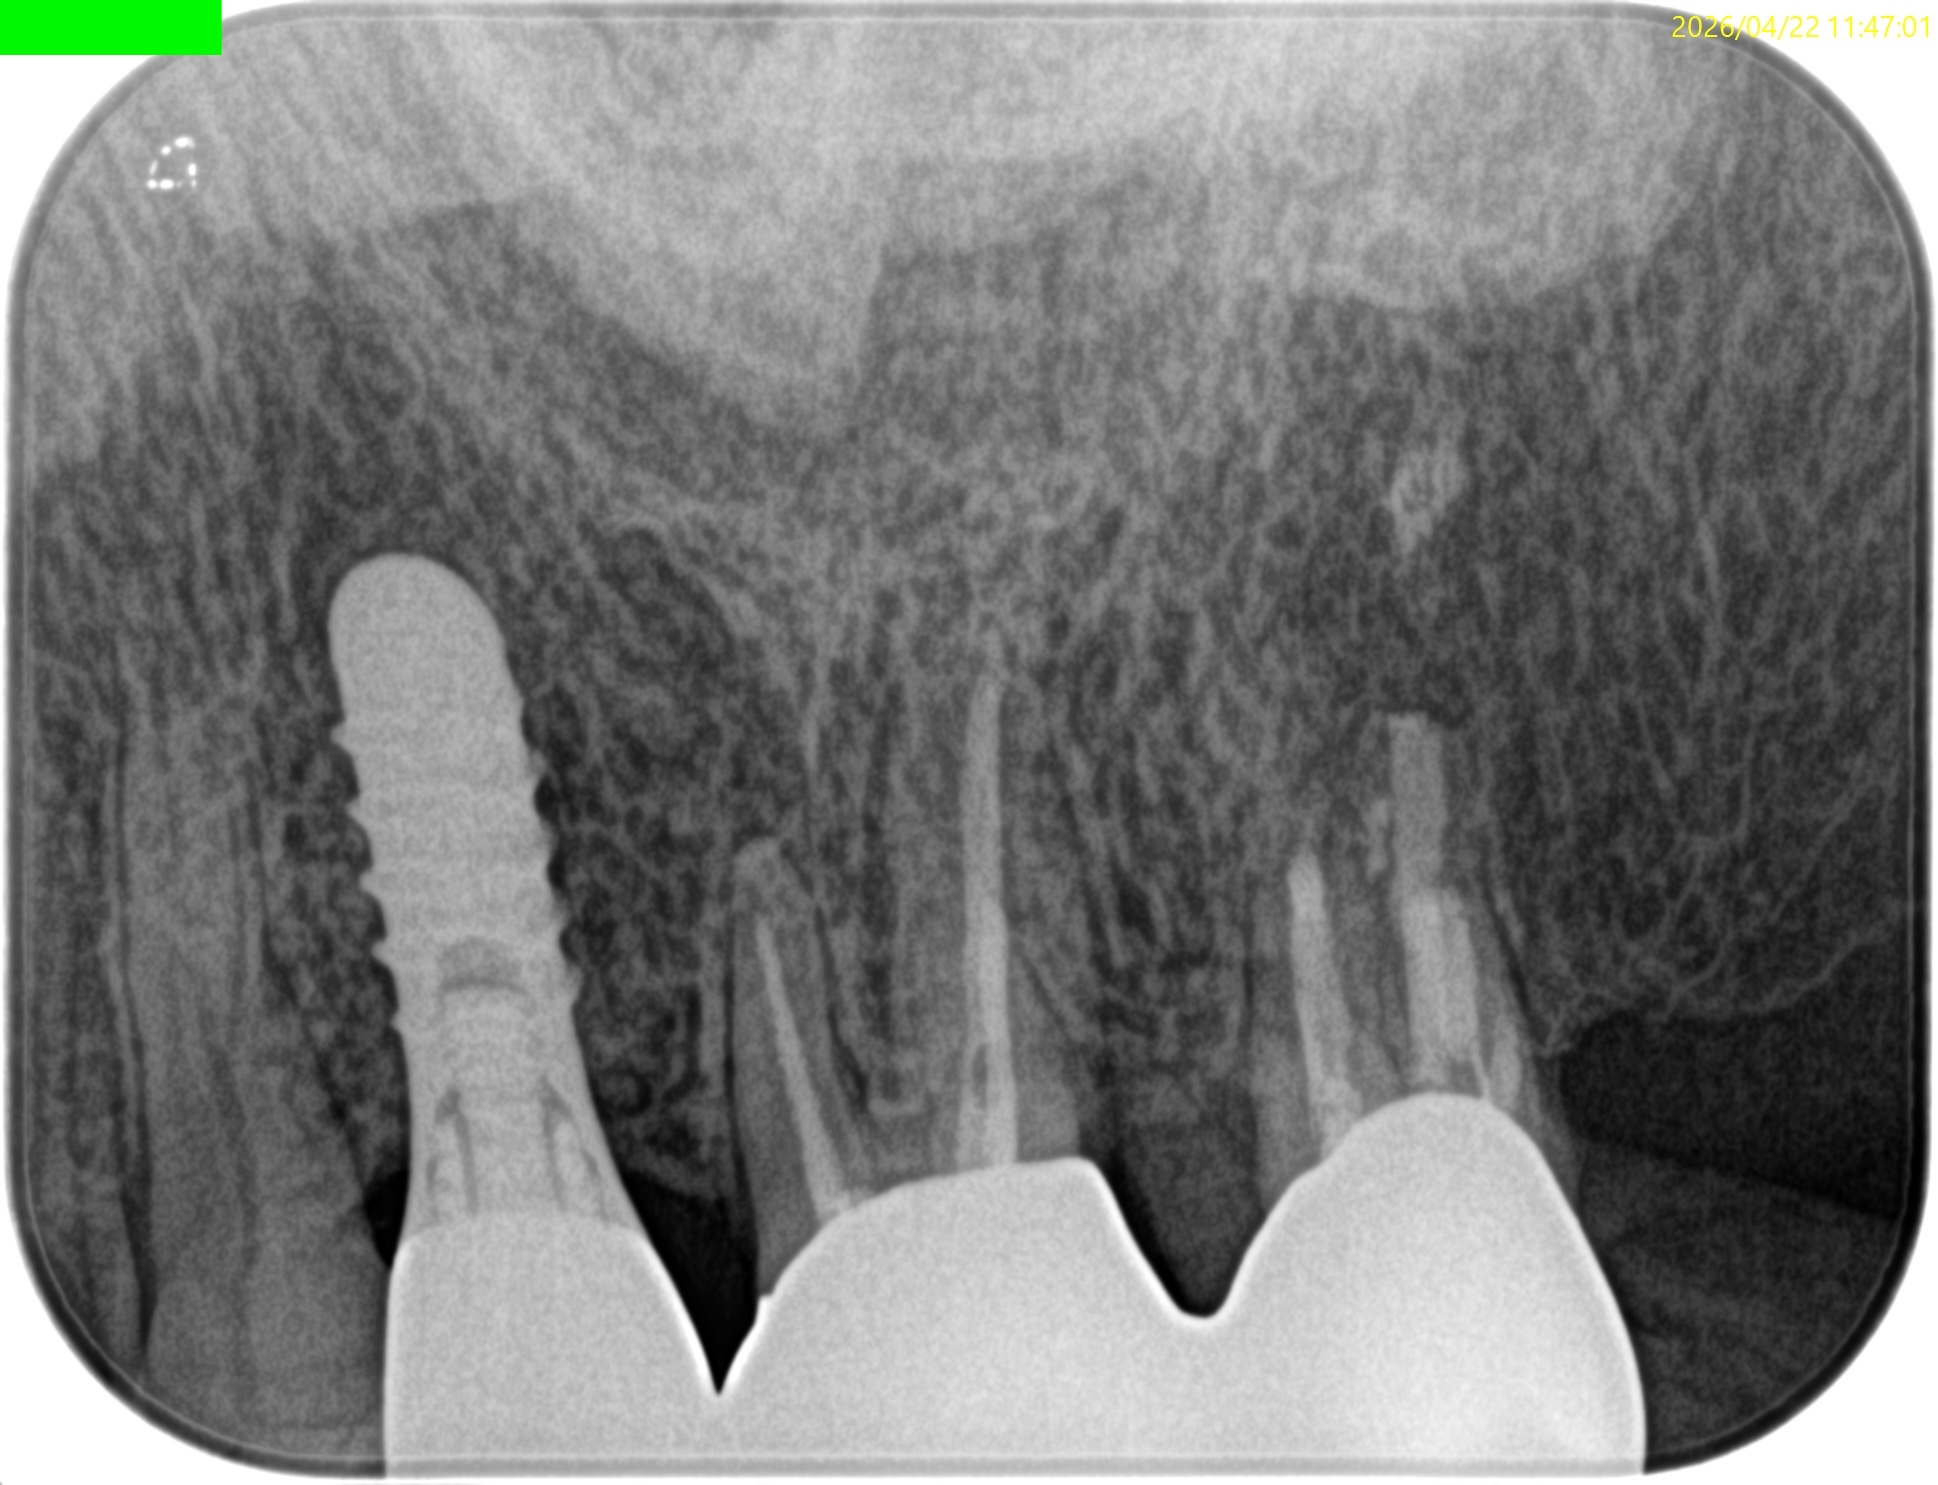

#15 Intentional Replantation 1yr recall(2026.4.22)

PA, CBCTを撮影した。

DBの破折ファイルは除去できていないが病変は消失している。